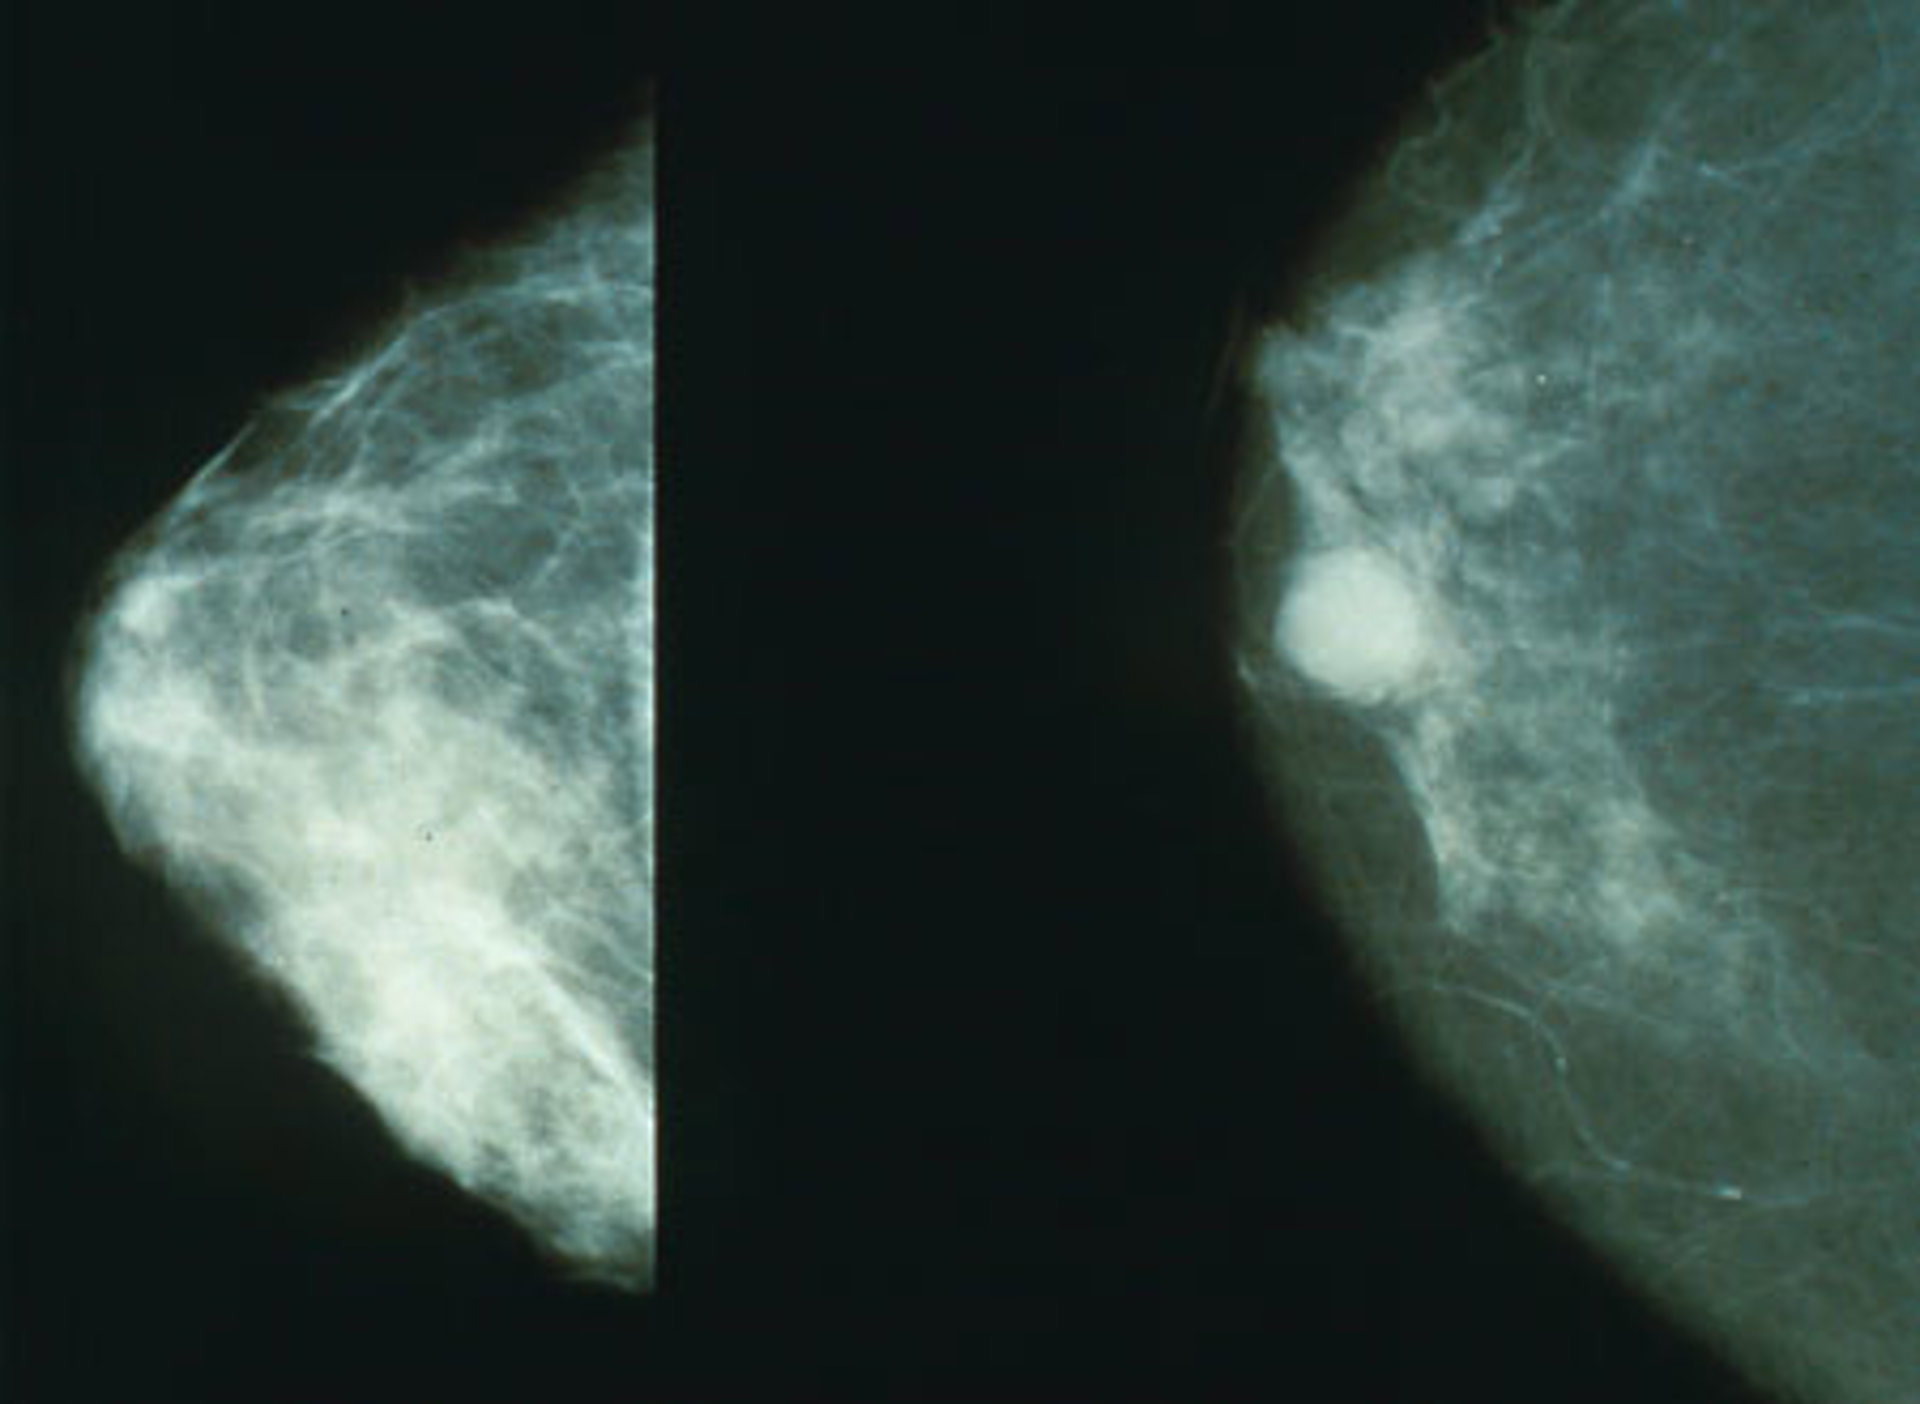

Cáncer de mama